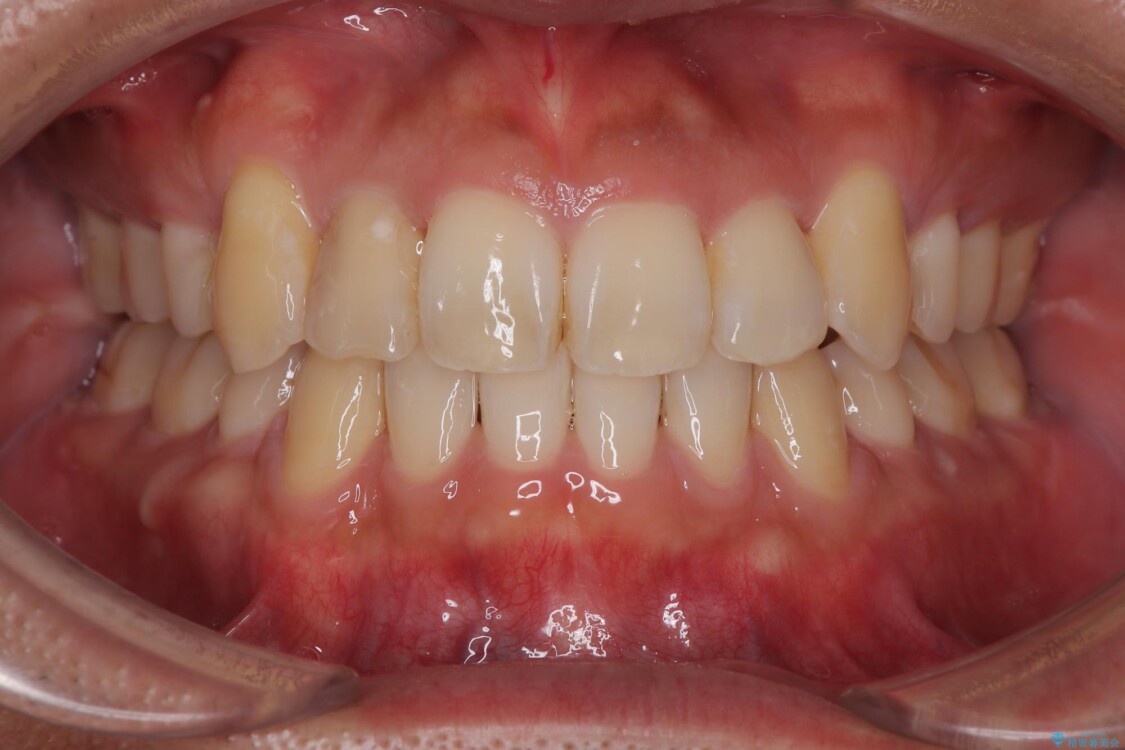

八重歯はきれいに整い、前歯もバランスよく収まり、横顔のラインも自然に改善されました。

治療後、患者様は「思い切り笑えるようになった」と大変喜んでくださいました。

治療後

• 八重歯と前歯のガタガタを抜歯矯正で治療|クリアブラケット使用例 治療後画像